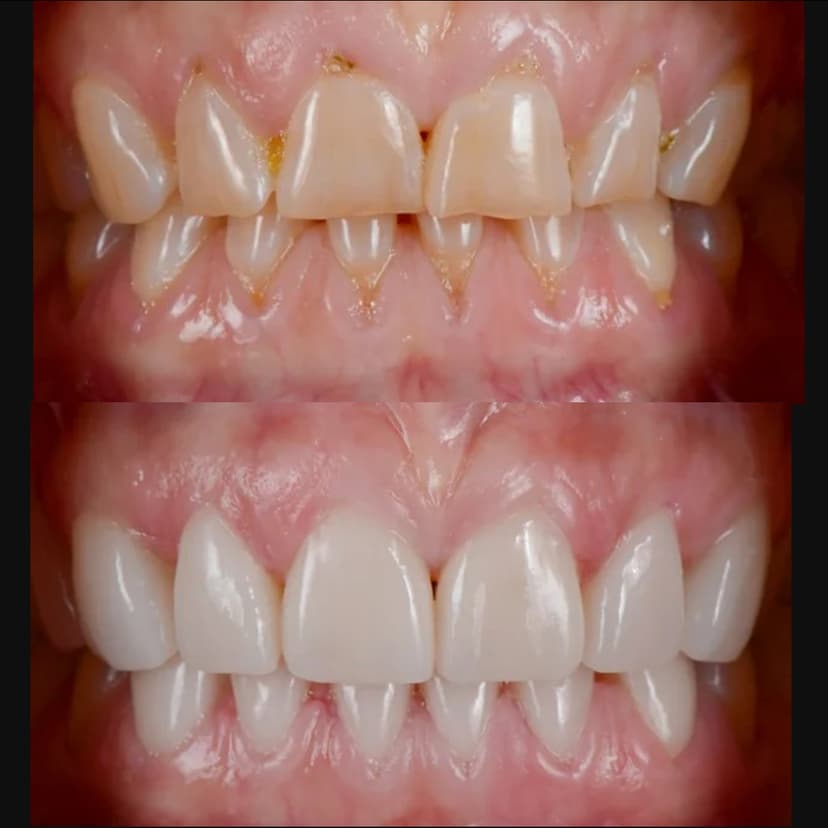

Complete smile transformation with multiple cosmetic procedures

Key Features: